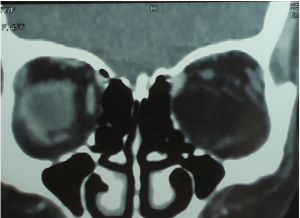

Bone remodelling may be present but no bony erosion. | Pleomorphic Adenoma. a & b). Non-contrast CT scan demonstrates well-defined, round to oval lesions, smooth in outline, associated with prominent scalloped lacrimal fossa (orange curved line) formation due to pressure without bone erosion in comparison to left orbit (orange arrows). Long-standing large tumours lobulations and radiolucent areas of cystic degeneration. |